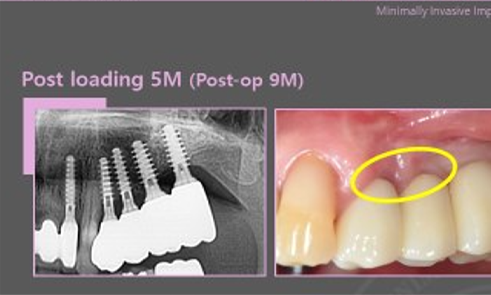

Tissue On-Growth

biologic width which is formed after implantation is not damaged again.

Immediate implant in narrow anterior ridge

Magicore implants need only 0.25 mm of buccal and lingual bone.